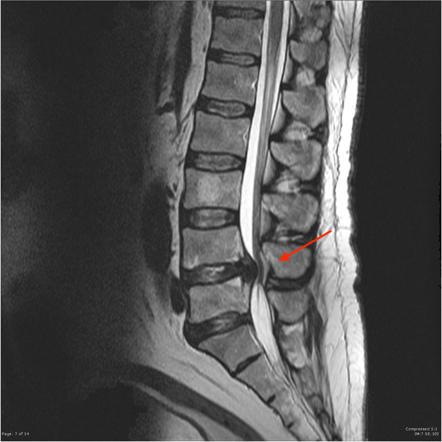

Ecco le immagini a raggi X della colonna vertebrale di una persona affetta da compressione vertebrale.

Ecco ora la radiografia di come dovrebbe presentarsi una colonna perfettamente distanziata.